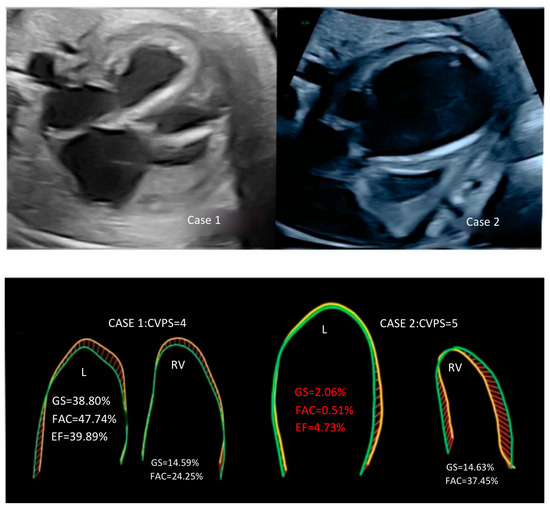

Background and Clinical Significance: This article explores the application of fetal speckle tracking technology in evaluating critical aortic stenosis (AS) in fetuses, highlighting its potential for predicting neonatal outcomes. Case Presentation: We present two cases of fetuses diagnosed with critical AS and associated complications at late gestation. Case 1 demonstrated preserved left ventricular function, as indicated by favorable global strain (GS), fractional area change (FAC), and ejection fraction (EF) values, despite critical conditions. This infant underwent successful postnatal interventions and was discharged after an extended NICU stay. In contrast, Case 2 exhibited severely compromised left ventricular function with significantly reduced GS, FAC, and EF parameters, leading to a tragic outcome despite intensive management. Conclusions: Our findings suggest that innovative echocardiographic parameters such as GS, FAC, and EF for the left ventricle are crucial in prognostic evaluations for fetuses with critical AS. The study underscores the importance of advancements in fetal cardiology and the need for further research to enhance prognostic assessments and improve clinical outcomes in affected neonates. Full article

Figure 1